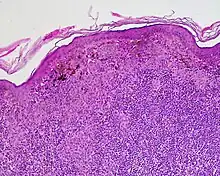

Halo nevus (also known as "Leukoderma acquisitum centrifugum," "Perinevoid vitiligo," and "Sutton nevus"[1]: 689 ) is a mole that is surrounded by a depigmented ring or 'halo'.

Halo nevi are also known as Sutton's nevi, or leukoderma acquisitum centrifugum. Halo nevi are named such because they are a mole (nevus) that is surrounded by an area of depigmentation that resembles a halo.

Halo nevi are associated with vitiligo. Sometimes the pale (hypopigmented) areas will spontaneously regress, and pigment returns.

The formation of a halo surrounding a nevi is believed to occur when certain white blood cells called CD8+ T lymphocytes destroy the pigment-producing cells of the skin (melanocytes).[2] The cause for the attack is unknown.[3]